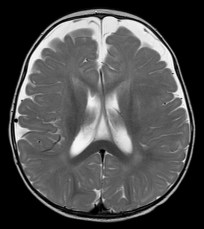

- l’échographie montre que le liquide est situé dans l’espace sous-arachnoïdien et non sous-dural, sachant que les deux peuvent co-exister. la valeur limite de la distance sinus sagittal- cortex est classiquement de 6 mm. les ventricules sont souvent légèrement dilatés également.

l’IRM identifie les veines et distingue l’épanchement sous-arachnoïdien du sous-dural qui lui est parfois associé. elle permet aussi de distinguer les macrocranies essentielles vraies des autres causes de macrocrânie : macrocéphalie vraie (syndrome de Sotos)